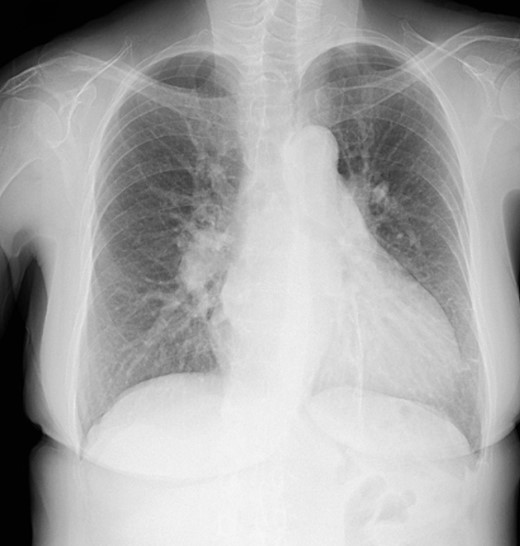

The patient was followed up as an outpatient since 2010 for incomplete AVSD and congestive heart failure by the Cardiovascular Surgery Department at our hospital. She did not wish to undergo surgery; therefore, we continued to follow her as an outpatient. Mitral regurgitation (MR) III-IV and mitral valve deviation was detected by echocardiography at approximately 2022, with worsening heart failure symptoms (New York Heart Association (NYHA) class III status). Echocardiography revealed an ejection fraction (EF) of 65%; severe MR; mean pulmonary artery pressure (PAP) of 32 mmHg; left-to-right shunt flow; left ventricular dysfunction (LVDd) of 48 mm; LVDs, 32 mm; and cleft mitral valve (Fig. 1). Chest radiography revealed a cardiothoracic ratio (CTR) of 58% and a costophrenic angle (CPA) sharp (Fig. 2). Cardiac catheterization revealed a Qp/Qs ratio of 2.6. Therefore, we performed a mitral valve repair and patch closure of the primum ostium defect.

Preoperative cardio echography showing fraction EF 65%, MR severe, mean PAP 32 mmHg, left-to-right shunt flow, LVDd 48 mm, LVDs 32 mm, and a cleft mitral valve.